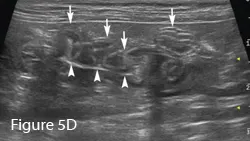

To differentiate normal centralized small intestine from pathologic intestinal bunching, a plastic or wooden spoon may be used to place pressure on the lateral abdomen to disperse the intestinal segments. This cat demonstrated corrugation (ie, undulating serosal margins) of a segment of small intestine, seen in some cases of linear foreign body ingestion causing intestinal plication.

Intestinal plication (arrows) may be seen via ultrasound; in some cases, linear foreign material (arrowheads) may be visible within the small intestinal lumen.